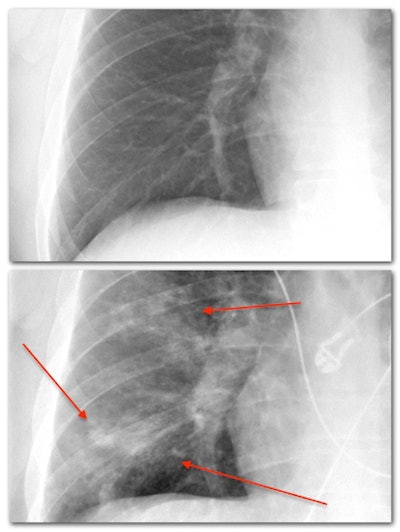

- Pulmonary edema: Pulmonary edema occurs when too much fluid accumulates in the lungs. Fluid leaks out of the blood vessels, most commonly from a back up of pressure in the vessels secondary to heart failure (cardiogenic pulmonary edema). Various other causes of fluid leakage are usually grouped together as "noncardiogenic" pulmonary edema, i.e., not caused by heart failure. Fluid initially accumulates in the interstitial tissues, resulting in an interstitial lung pattern. As the disease process worsens, fluid spreads into the alveoli and airways, causing consolidation.

- Interstitial lung pattern: An interstitial lung pattern refers to subtle thin lines and small dots interspersed throughout the lungs. Sometimes radiologists will use the term "reticular" to mean lines and "reticulonodular" to mean lines and dots together. To understand this appearance, it's time for another lung anatomy lesson. The interstitial tissues are located between the airways and alveoli previously described, and they consist of tissues that help support the lung, including blood vessels. On a normal chest x-ray, the interstitial tissues are too small to see. Only when they are abnormally thickened do they manifest as thin visible lines. Dozens of conditions can result in this appearance, with some common causes including pulmonary edema, pulmonary fibrosis, certain types of pneumonia, and autoimmune and allergic conditions.